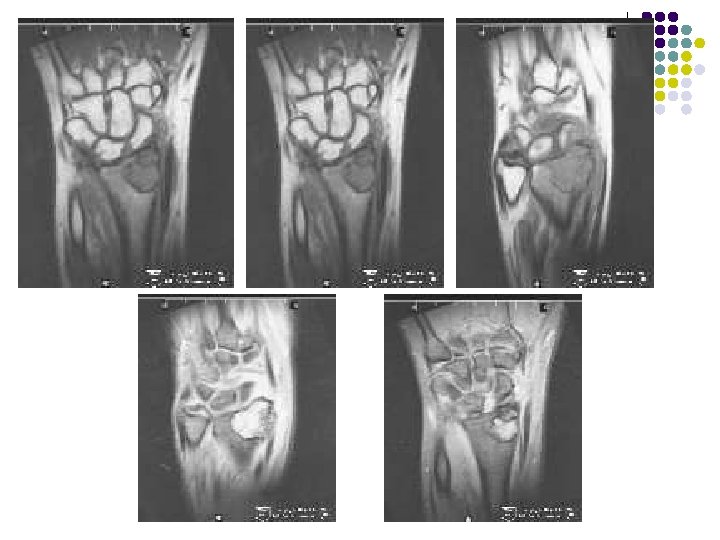

Radiographic Findings: Wrist Films: l Lobulated lytic lesion of the distal radius abutting the articular surface and extending from the epiphysis into the proximal metaphysis. l matrix calcification are seen. MR: l The lesion demonstrates low signal on T 1 weighted images and high signal on T 2 weighted images with rings and arcs compatible with chondroid matrix. l No extra-osseousoft tissue mass is seen.

Lucent area with well-defined margins in region of epiphysischondroblatoma in 11 yrs old boy Coronal reconstructed ct Coronal t 1 confirmsmetaphyseal weighted extension